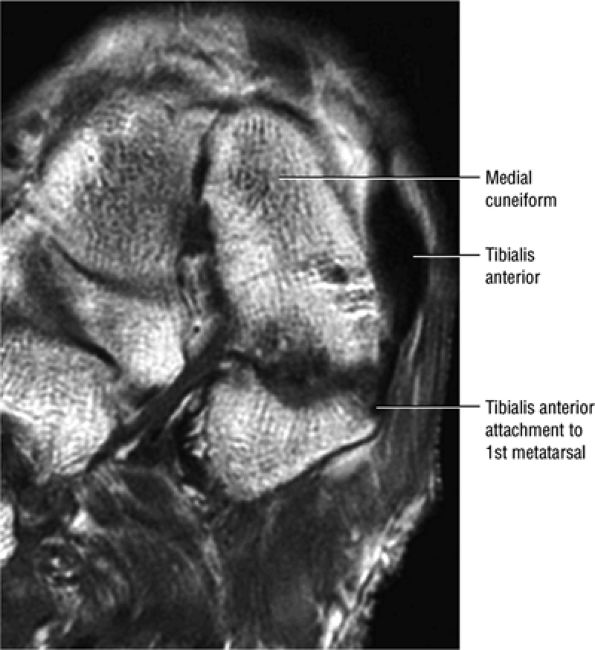

The anterior muscles of the leg are the tibialis anterior (Fig. 5.2), the extensor hallucis longus (Fig. 5.3), the extensor digitorum longus (Fig. 5.4) and the peroneus tertius (Fig. 5.5).

![]() |

|

FIGURE 5.2 ● TIBIALIS ANTERIOR The tibialis anterior muscle functions eccentrically after the heel strike to control deceleration of the foot and concentrically after the toe-off in ankle dorsiflexion. In runners and hikers, paratenonitis is associated with the use of excessive eccentric contraction during midfoot and forefoot impact on downhill slopes. Paratenonitis is also associated with direct mechanical irritation from ski boots or hockey skates. The tibialis anterior dorsiflexes and inverts the foot.